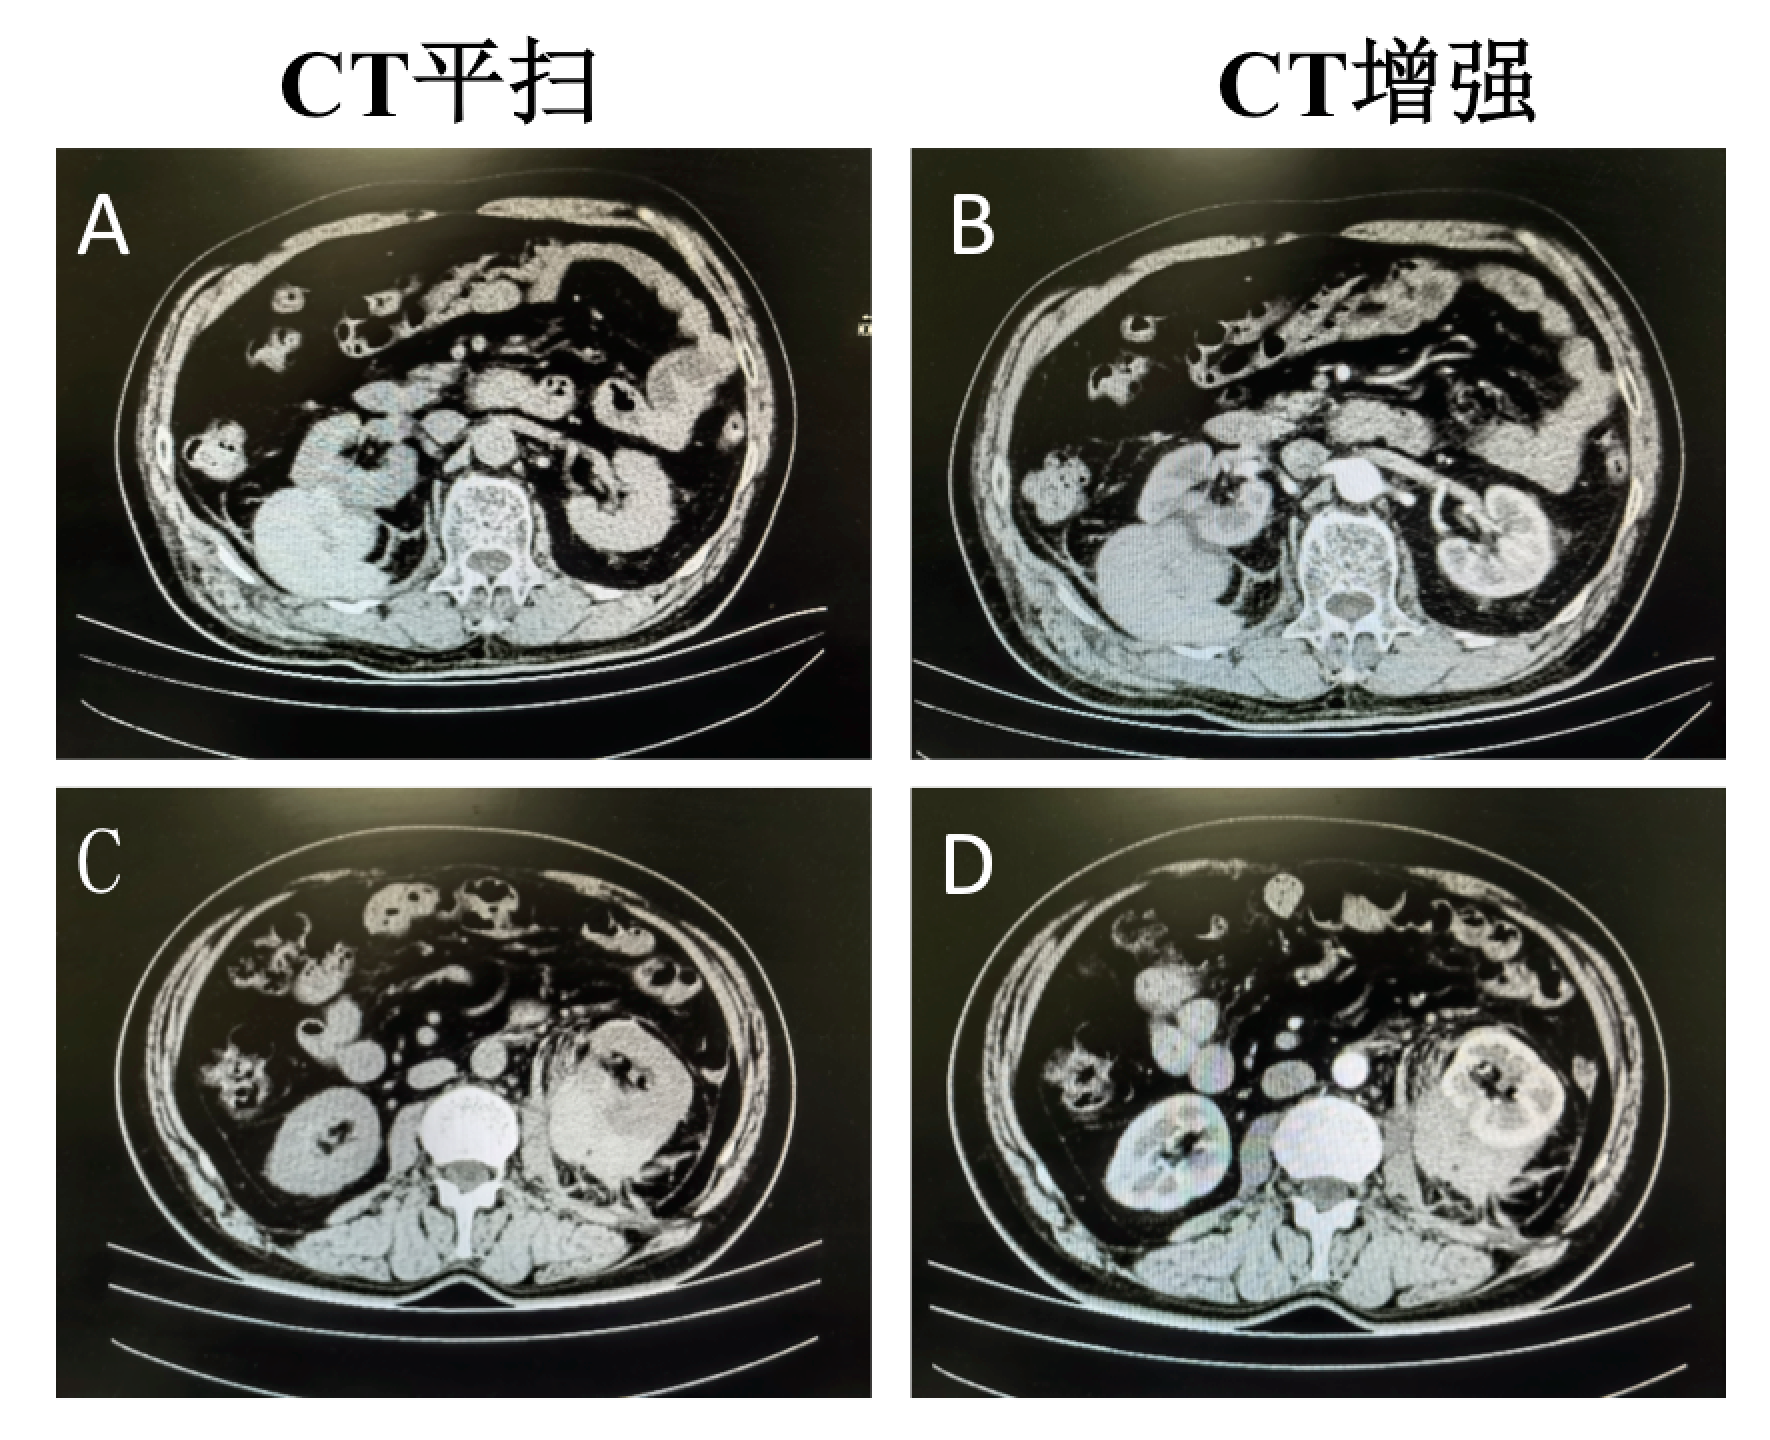

腹部实质性脏器外伤的ct表现

图片尺寸1080x810